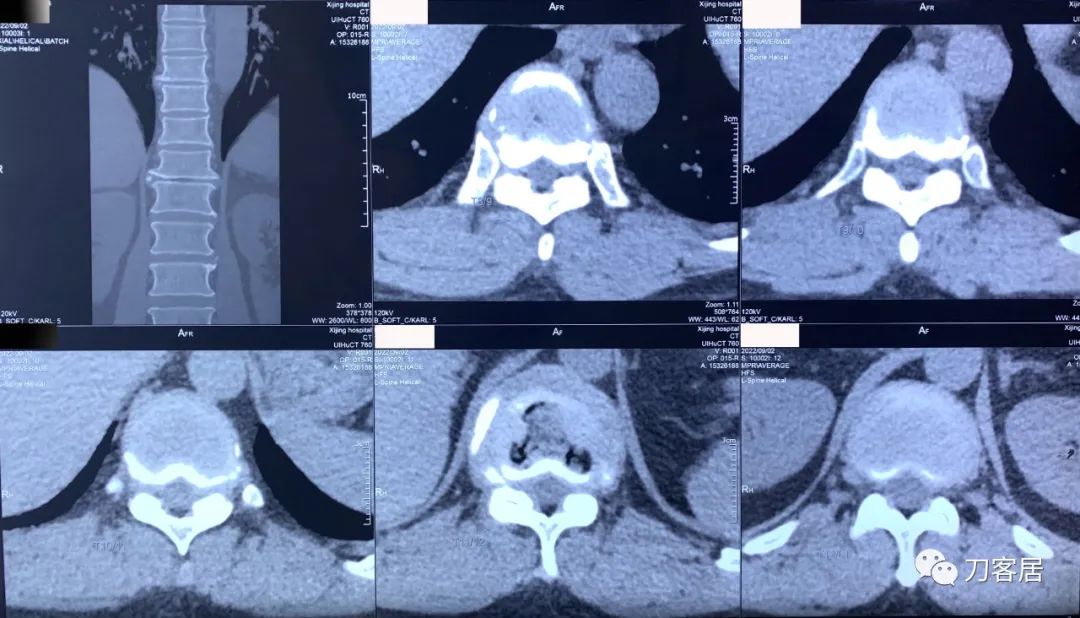

图20. 20220902西京医院胸腰段三维CT扫描重建01,提示胸11-12椎间隙变窄,椎体前后缘骨质增生,有椎管狭窄,但并不那么严重。

图21. 20220902西京医院胸8-腰1三维CT扫描重建02, 胸8-9, 胸9-10,胸10-11,胸11-12,胸12-腰1椎间隙CT扫描,椎管狭窄存在,但并不严重。

图22. 20220902西京医院胸8-腰1三维CT扫描重建报告